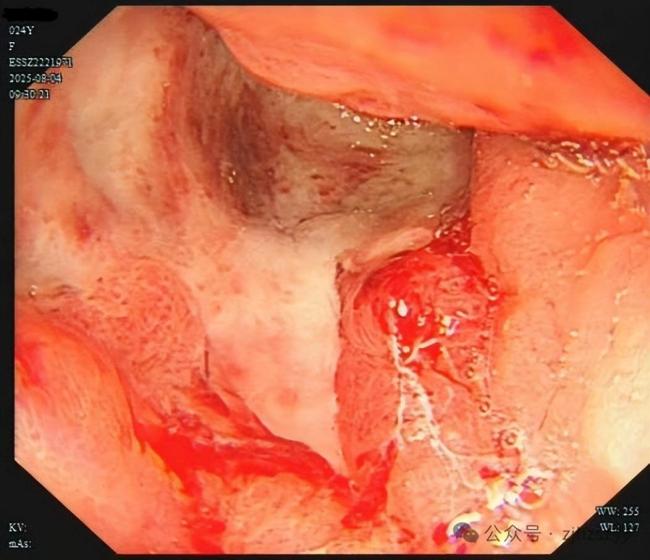

直到她开始频繁出现黑便,并在片场拍戏时几次呕血,才被同事紧急送往医院急诊。医生立即为她安排了急诊胃镜检查,发现她整个胃窦被巨大的溃疡占据,黏膜组织变得僵硬、缺乏弹性。随后的活检结果显示,她患上了胃印戒细胞癌。

小雯所患的印戒细胞癌被称为“胃癌之王”,是胃癌中一种恶性程度极高的类型,占胃癌恶性肿瘤的10%左右。这种癌症的特点是隐匿性强,在胃镜下表现不明显,识别非常困难。早期患者很多没有明显的症状,或者症状和普通消化道疾病相似,极易被忽视。多数发现时已是晚期,且具有很强的侵袭力,易转移,病情进展快。晚期患者的生存期一般只有6-12个月,5年生存率几乎为零。